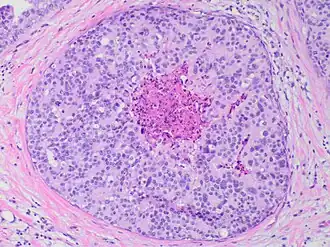

![Histopathology of high-grade DCIS. H&E stain. RBC = red blood cell.[25]](./_assets_/Histopathology_of_high-grade_DCIS.png)